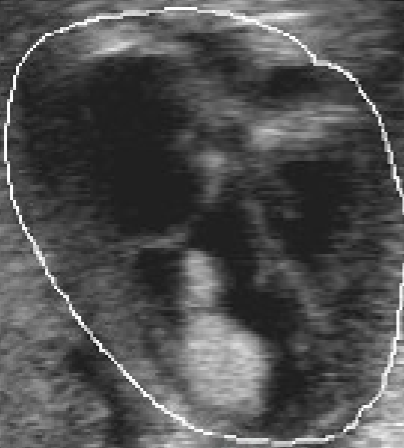

Rhabdomyoma

found at birth and <1 yr

70-90% have multiple tumors

associated w/ tuberous sclerosis

found in ventricular walls

more common in RV

solid, echo-dense mass protruding into ventricular cavity

mortality d/t blood flow obstruction

have been reported to recede over time